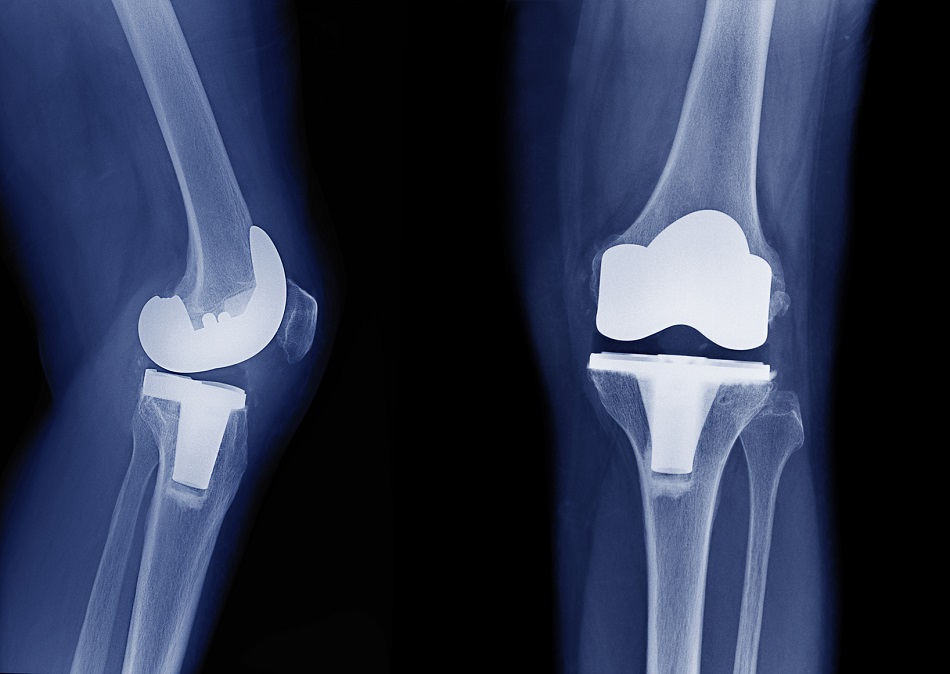

Artroplastia de rodilla: eficacia de la rehabilitación domiciliaria

En pacientes con reemplazo total de rodilla, un programa de rehabilitación de 10 días con el paciente internado no fue superior a un plan de seguimiento domiciliario. JAMA, 14 de marzo de 2017